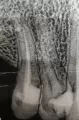

5 дней назад мне поставили 3 пломбы на разных зубах, был небольшой кариес. Нервы не удаляли, пародонтоза нет, легкое опущение десны. И вот у меня появилась резкая чувствительность этих зубов, в основном на холодное. На одном из запломбированных зубов легкая чувствительность была раньше, и она резко усилилась.

Это вполне нормальная реакция, зубы потревожили, препарировали кариес.

Можно провести глубокое фторирование вылеченных зубов, это гораздо снизит Ваши неприятные ощущения.